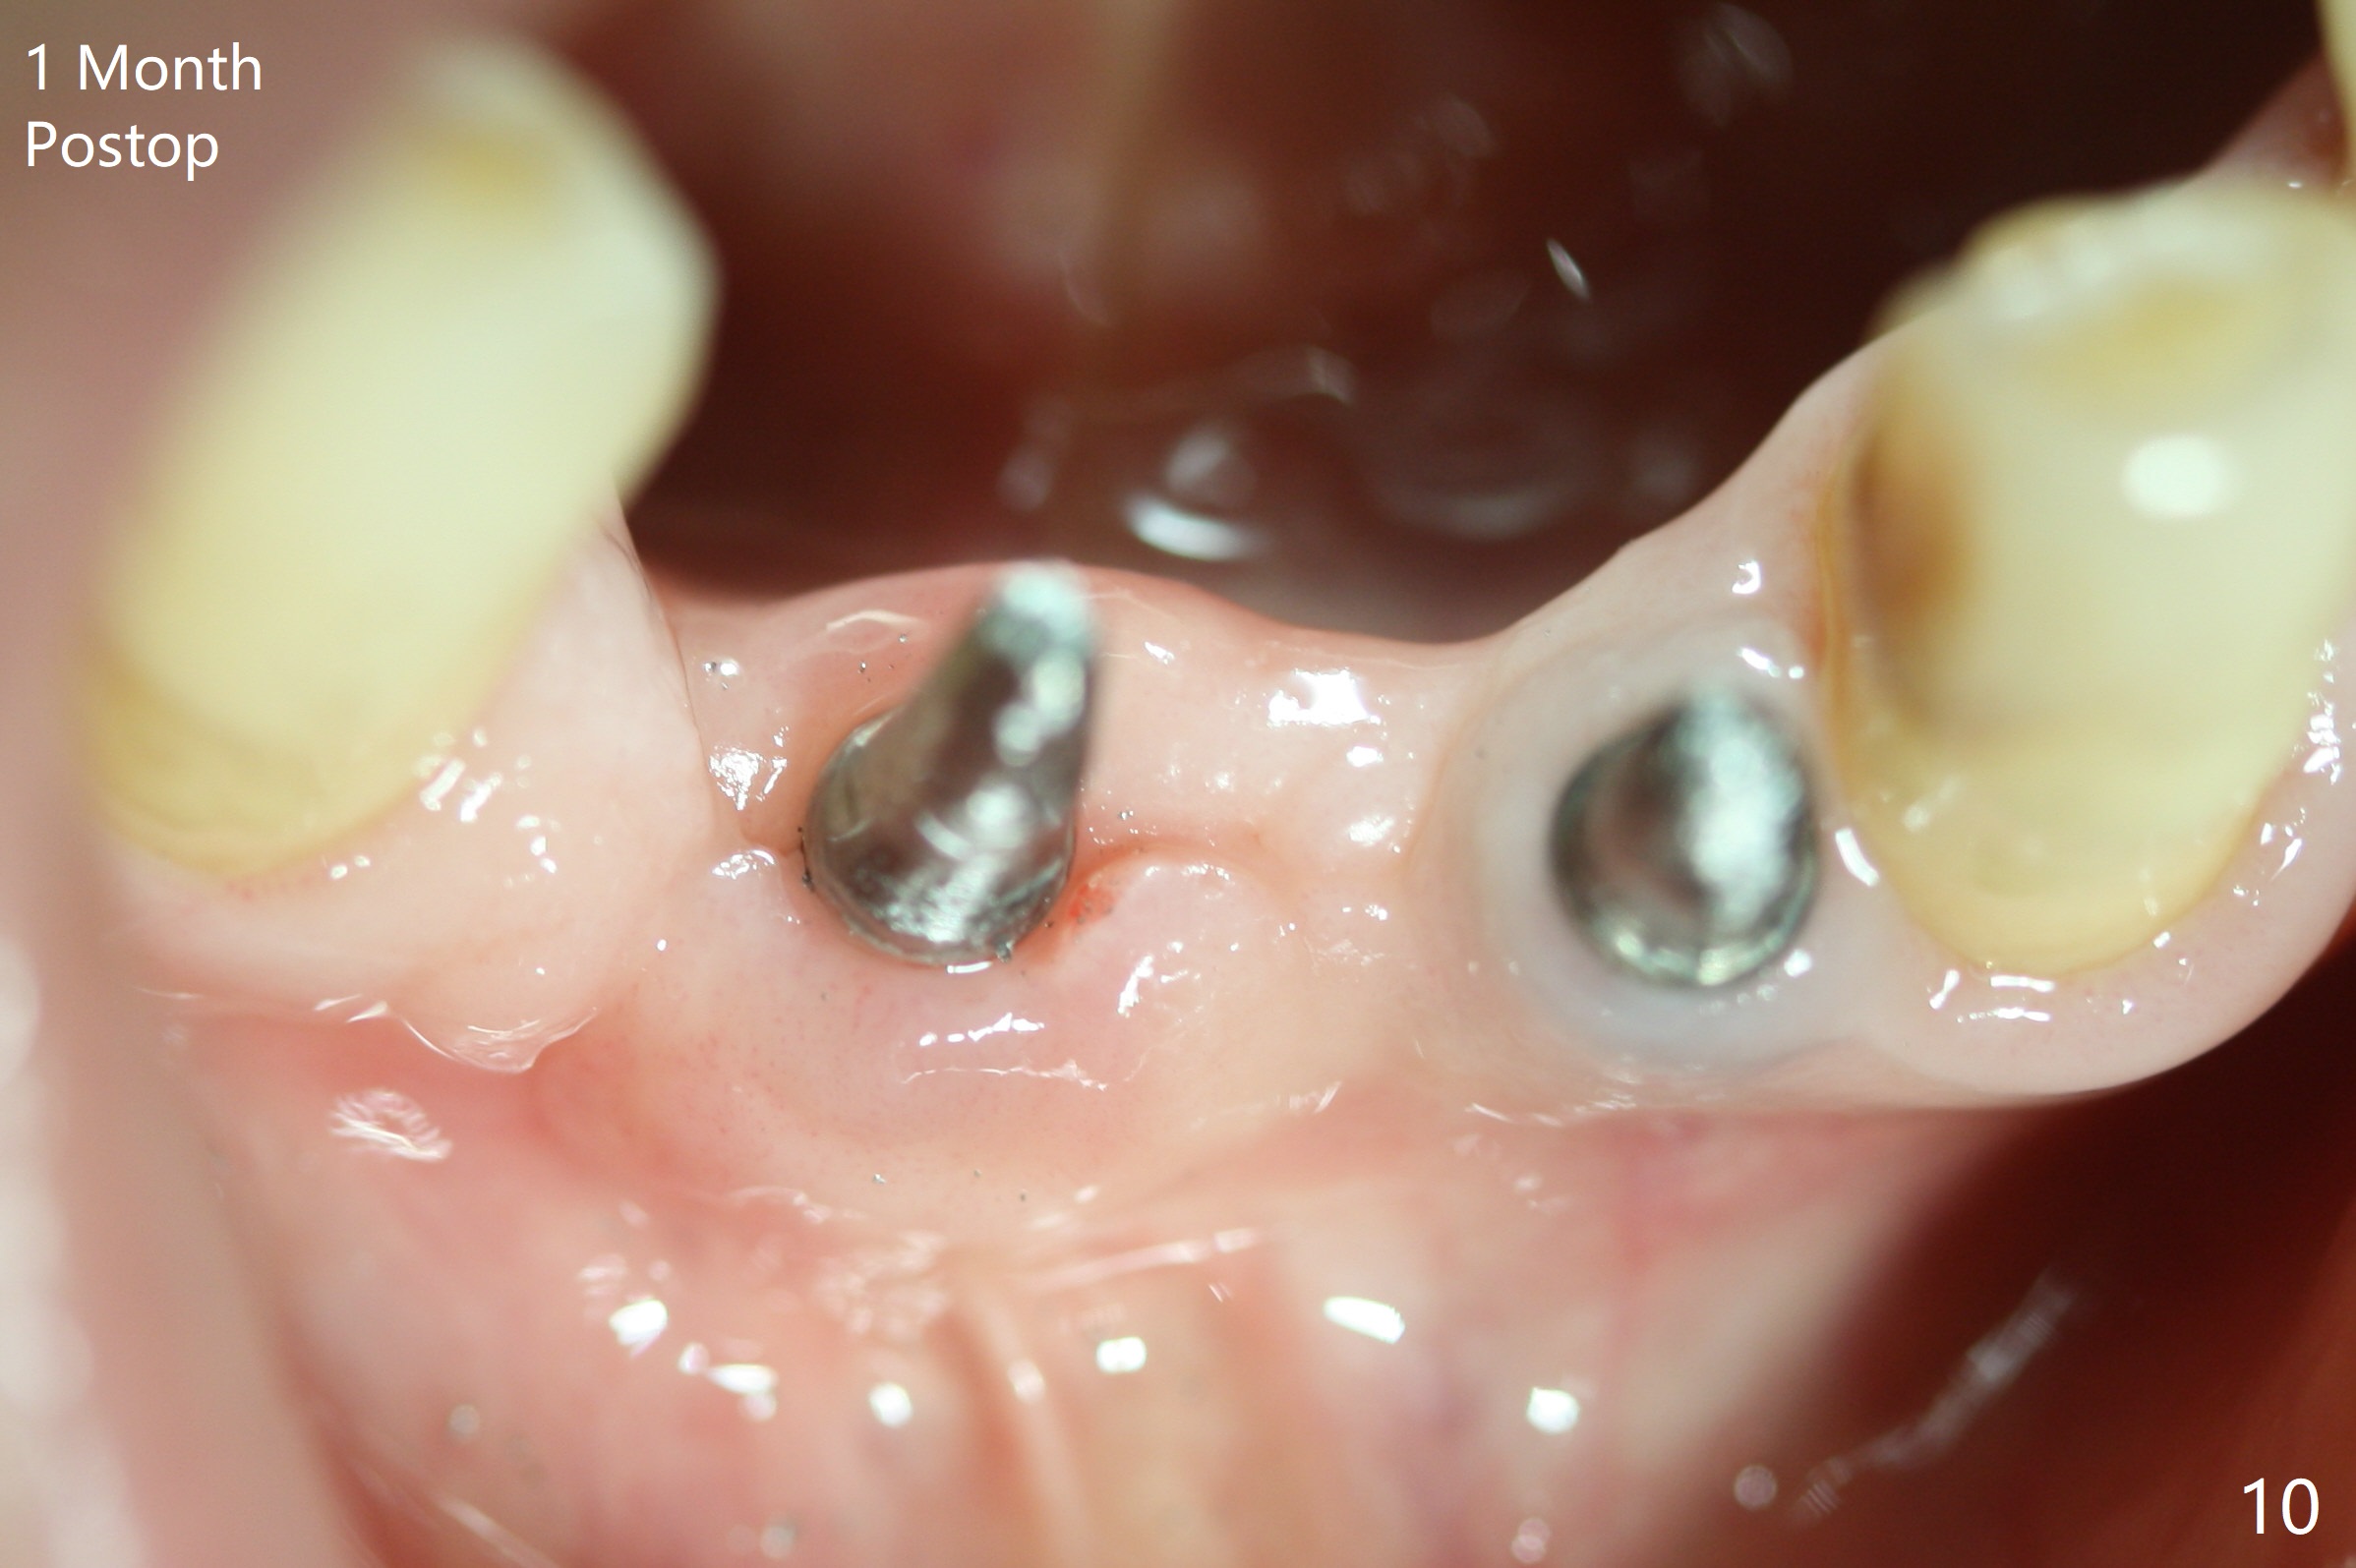

After removing #23-26 FPD and the 3x14 mm 1-piece implant at #26 (Fig.1,2 *), a new osteotomy is initiated in the narrow ridge (after ridge top reduction) approximately at #25 (Fig.2 <). Following placement a 2x10(4) mm implant at #25 (Fig.3-5) and Osteogen plug in the osteotomy at #26, Vanilla graft is placed around the implant, especially buccal. Periodontal dressing is applied after suturing. The buccal and lingual flaps are erythermatous and edematous without pain 8 days postop (Fig.6). The wound seems to be healing 2 weeks postop (Fig.7), no sign of osteonecrosis. With placement of a 2 mm implant at #25 (Fig.8 (>: bone graft buccally)), the buccal plate remains normal in thickness. When a 3 mm implant is placed at #23 (Fig.9), approximately 4 threads appear to be exposed (between arrowheads), partially due to the thick lingual plate (*).

The wound at #25 seems to heal 1 month postop; after prep (Fig.10,11), a provisional FPD is fabricated. Impression is taken for surgical guides of UL and LL implants. The patient requests early final restoration (Fig.12). The small implant placed lingually (Fig.12 *, 2 mm) is associated with the pleasing gingiva in color, as compared to the 3 mm one at #23 with the metal shaded gingiva.